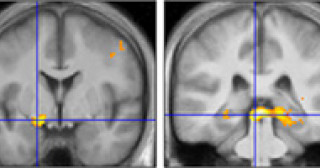

負の経験から学ぶ脳のメカニズムを発見 -嫌なことを避ける学習のために二つの脳領域が役割を分担-

視線が無意識で注意をそらす神経メカニズムを解明